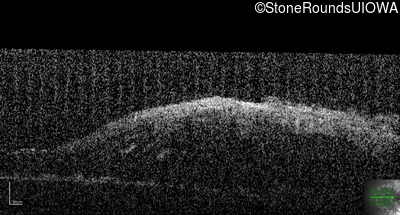

This 9 year old male was noted to have some crossing of his eyes at 2 months of age and the eye exam which followed identified a retinal lesion in the right eye. When he was six years old an epiretinal membrane was noted in his left eye. Two years later it was decided that it was a thin hamartoma in that eye as well. He underwent neuroimaging at age 7 which identified bilateral acoustic neuromas.